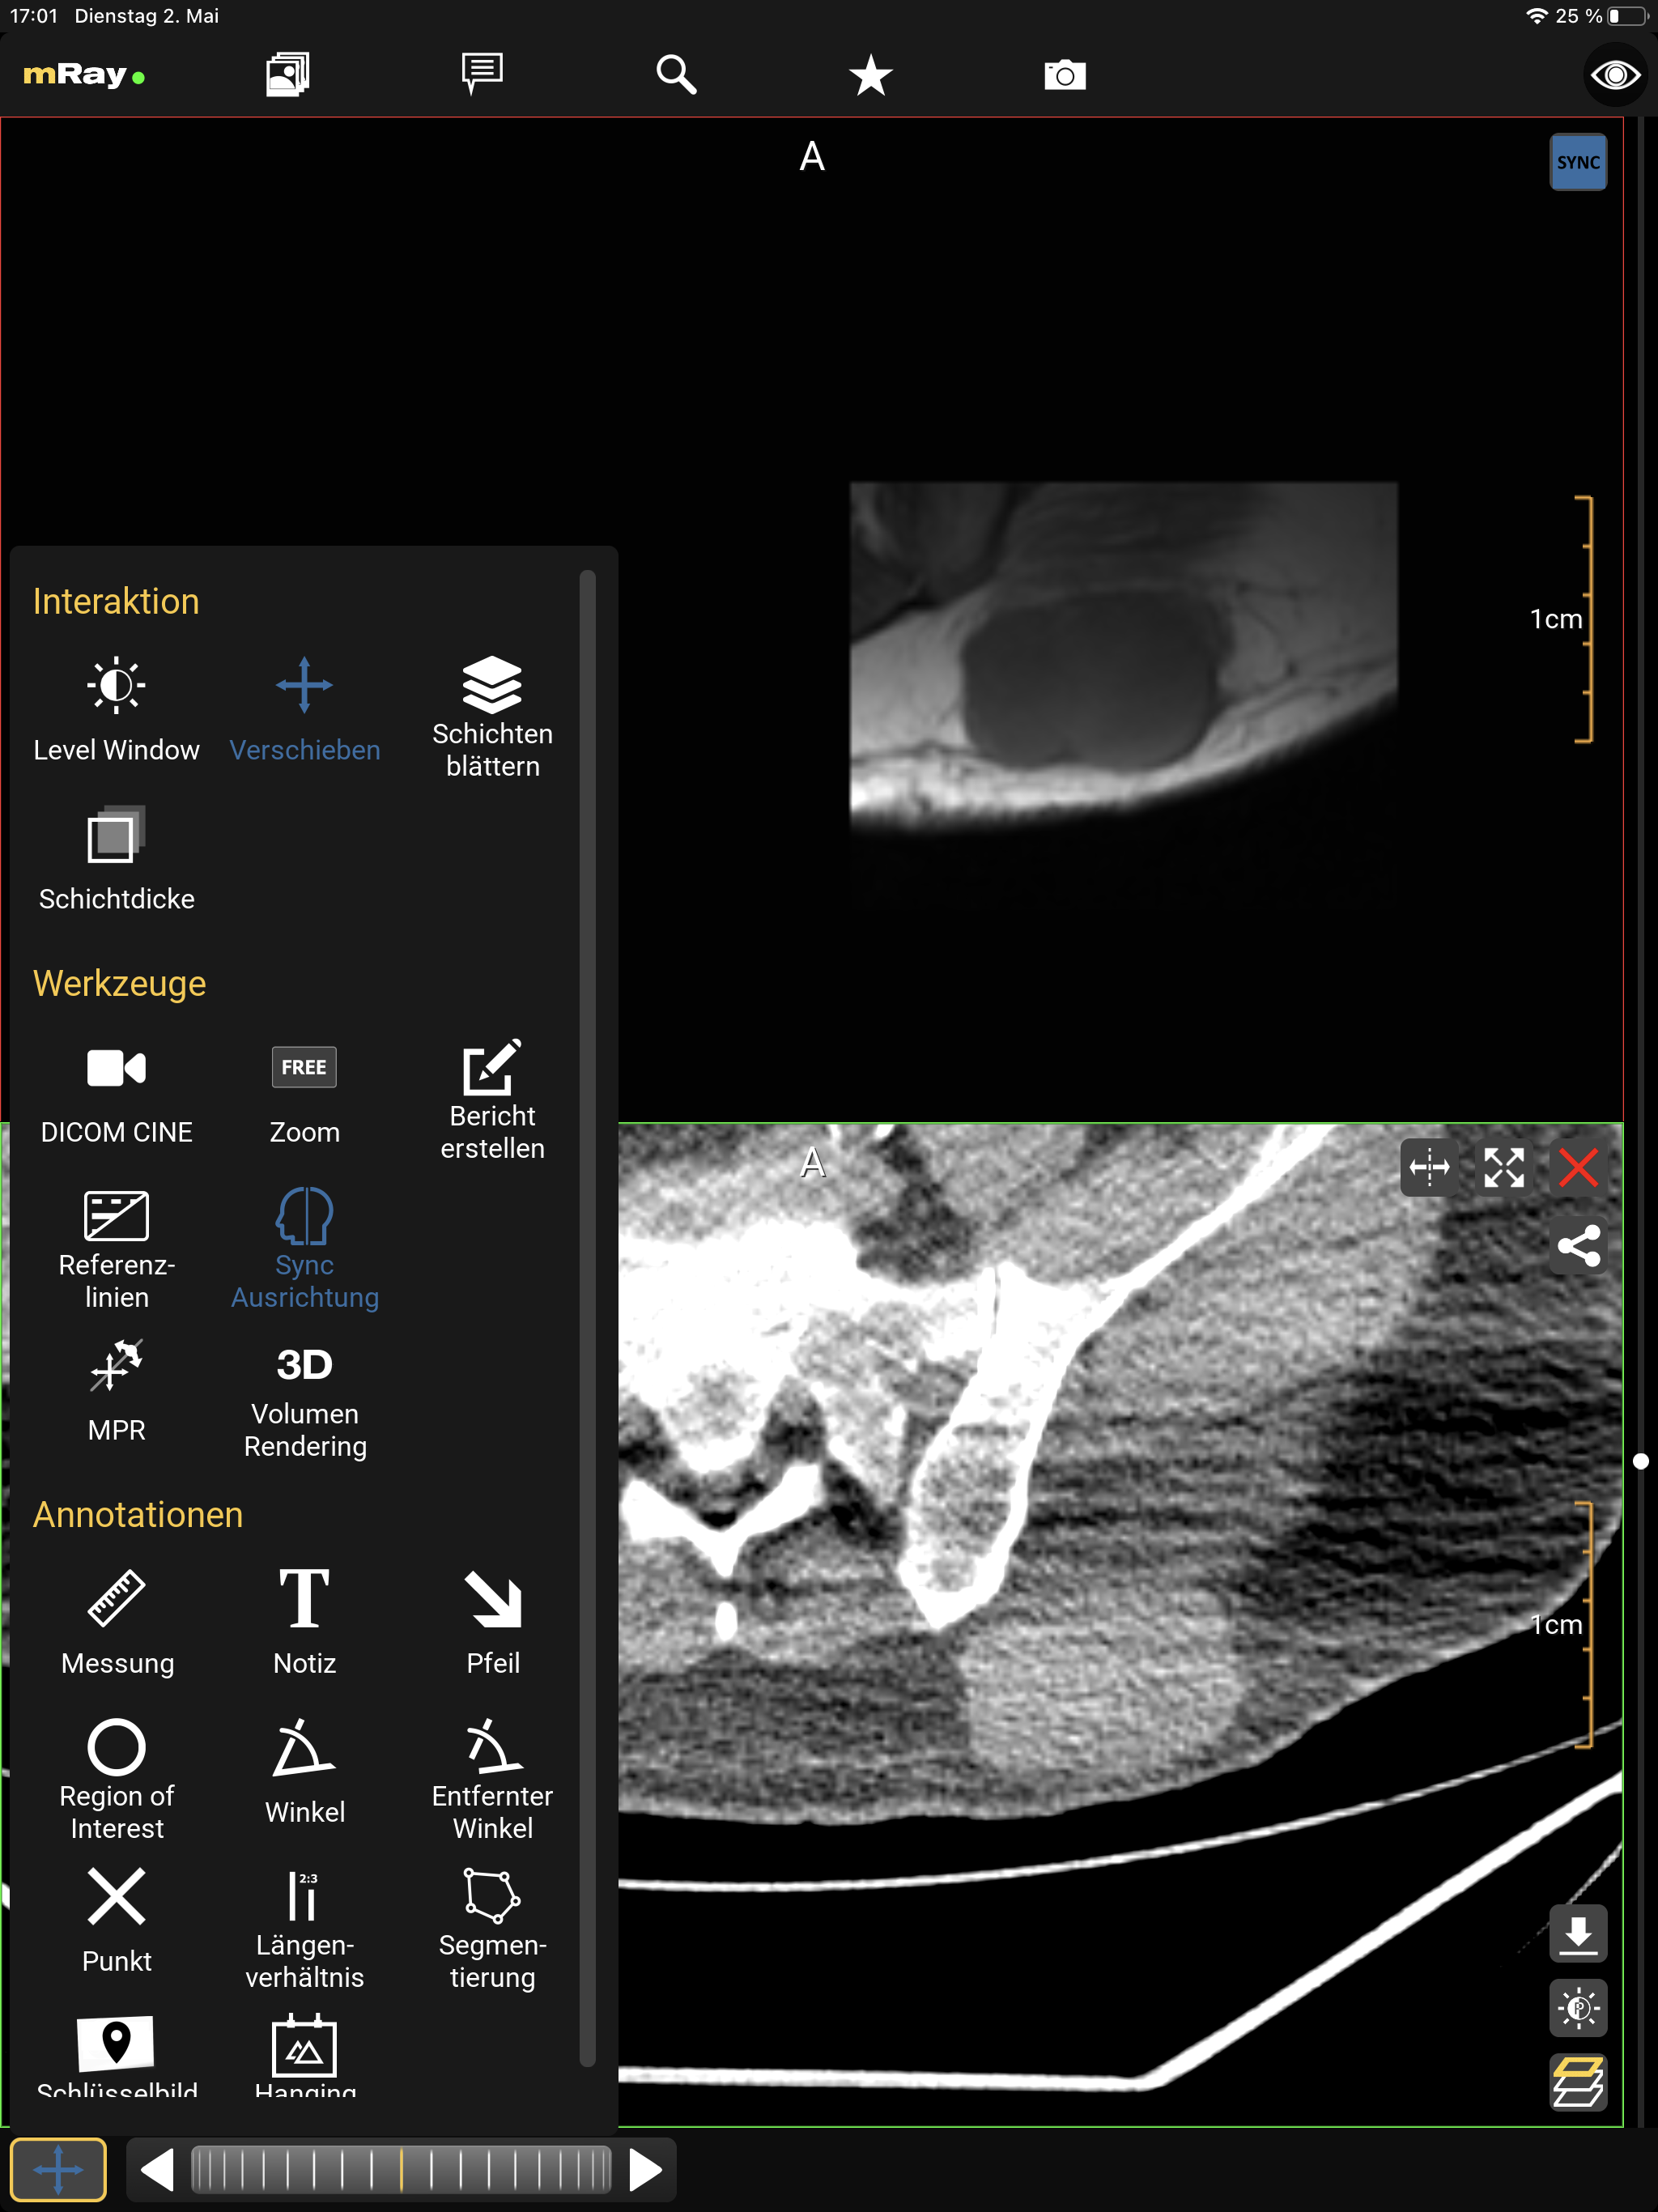

10.5. Toolmenu

You can select the following tools from the toolmenu:

-

Interaction

-

Level Window: With the level window tool you can modify the grayscale values and brightness of the view (Viewcontrol).

-

Panning: The panning tool allows you to pan, increase and decrease the size of the image. This tool is selected by default

-

Slice scrolling: You can scroll through the slice images via slice scrolling (see Interactionbar and Scrollbar). Scrolling happens via vertical movements on the image with the left mouse button pressed or by touch.

-

Thickness: Maximum intensity projection (MIP). View multiple slices at once (slices are superimposed). A maximum of 11 slices can be superimposed on each other.

-

-

Tools

-

Zoom: Zoom the image in and out in the preselected 'FREE' mode. By tapping the tool it will zoom the image to one of the prefabricated zoom levels in the following formats: 1:1, 1:2, 1:4 and 'FREE'.

-

Create report: Creates a structured report draft. See Report workflow for more details.

-

Reference lines: Switch between the different modes for displaying reference lines

-

MPR Display all MPR views of active dataset and enable plane control by dragging reference lines. (Arbitrarily oriented MPR)

-

SyncAlign Automatically align the patient position of one or more of the available datasets. (Synchronized Alignment)

-

Volume Rendering Visualize the active view’s dataset as a 3-dimensional volume. (Volume Rendering)

-

Annotations

-

Measurement: Create measurements on a slice of the image data set.

-

Note: Place a note on a slice of the image data set.

-

Arrow: Place an arrow on a slice of the image data set to highlight important regions.

-

Region of interest: This tool allows to mark a region of interest with an elliptical selection which shows information about the selected region imagedata.

-

Angle: Place an angle measurement on a slice of the image data set.

-

Remote angle: Allows to measure an angle (like the angle tool) between two lines.

-

Point: Place a cross on a slice of the image data set.

-

Length ratio: Show the length ratio between two lines.

-

Segmentation: Create a manual segmentation.

-

Save keyimage (to PACS): Saves the current view with all Annotations. The original dataset will not be touched. Optionally the keyimage will be uploaded to the PACS if your license supports the 'PACS upload' and it is properly configured.

-

Save Hanging: Save actual slices position and orientation from all view for future use.

-

List of annotations: Contains all annotations you added to the image. By long pressing an annotation in the list, more options such as multi-select, rename and delete will appear.

-

|

The selected interaction method is kept across studies. |